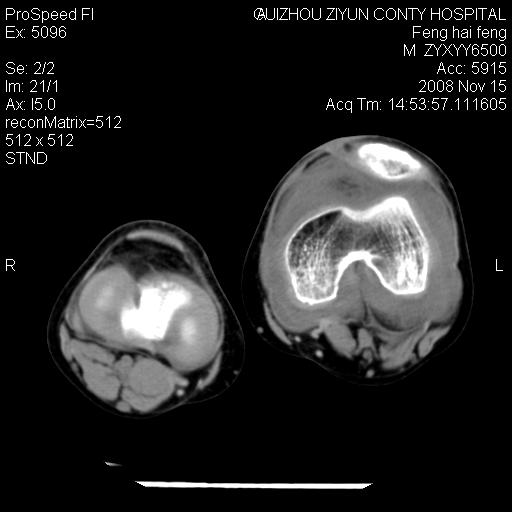

标题: CT16656:M 14Y 左膝关节肿胀一年余。其余病史不详。 [打印本页]

标题: CT16656:M 14Y 左膝关节肿胀一年余。其余病史不详。

考虑左侧髌骨结核;左膝关节滑膜肿胀、增厚,关节囊积液。

左膝滑膜型关节结核可能性大!支持!滑膜型关节结核主要ct表现:关节囊肿胀,积液,关节面见小破坏灶,并见点状死骨!

好大的左腿!考虑左侧髌骨结核,左膝关节滑膜肿胀、增厚,关节囊积液。

左侧髌骨结核;左膝关节滑膜肿胀、增厚,关节囊积液